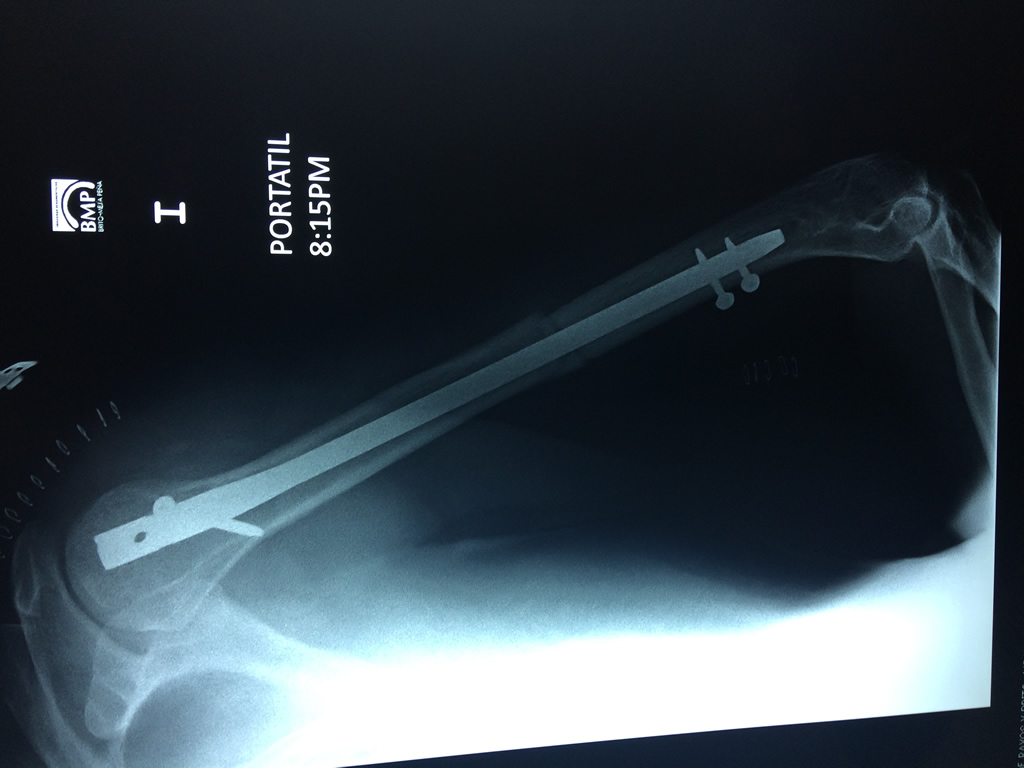

El Húmero (en latín, humerus) es el hueso más largo de las extremidades superiores en el ser humano. Forma parte del esqueleto apendicular superior y está ubicado en la región del brazo. ... El extremo proximal del húmero tiene la cabeza, cuellos quirúrgico y anatómico y tubérculos mayor y menor.